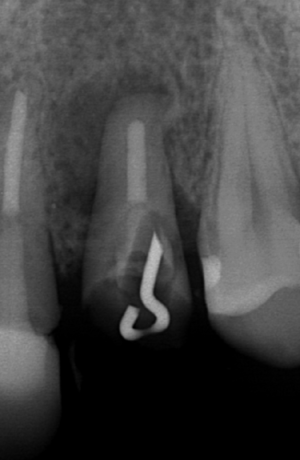

健全な歯根膜を利用して挺出、回転させ、こつの再生を促す。

挺出終了、180度回転させて歯の安定を待つ きれいに骨が再生している